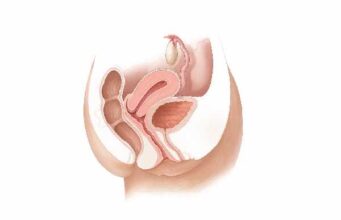

Discover the wonders of the human body, from its fundamental elements to the intricate systems that sustain life. This section explores the anatomy, physiology, and functions of various body parts, providing insights into our movements, thoughts, emotions, and interactions with our surroundings.